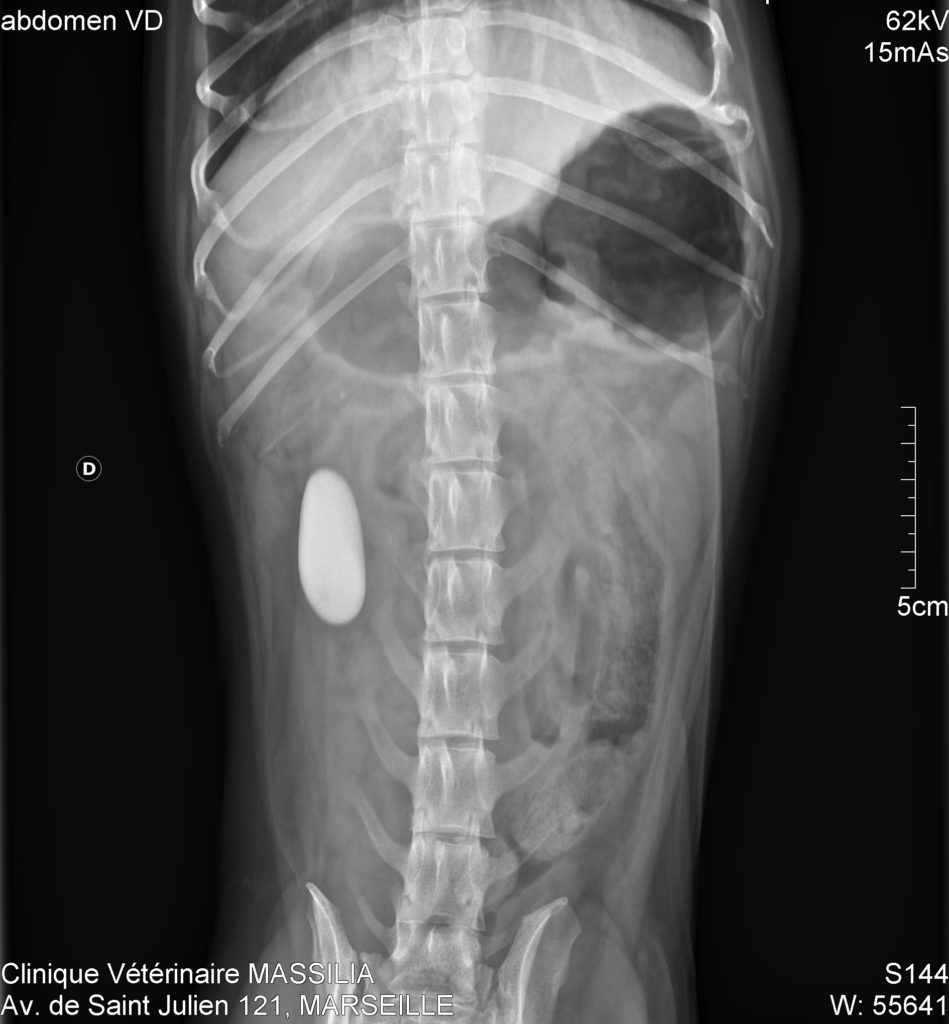

From www.vetpixel.com

Cas Un cas de jabot oesophagien secondaire a une persistance du Jabot Oesophagien Chat L’hypomotricité oesophagienne, une prédisposition génétique du siamois, est une des causes de mégaoesophage. Une prédisposition raciale est constatée chez le. Oesophagite chez le chat et le chien : Dans ce cas, il est fréquent que le chat ait bon. Le jabot oesophagien est une dilatation localisée de l'oesophage qui résulte d'une malformation vasculaire congénitale (persistance du 4 ème. Chez le. Jabot Oesophagien Chat.